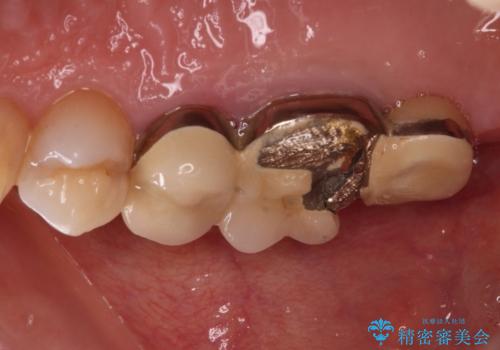

- 歯が欠損したままの奥歯のクラウンが欠けているとのことで来院された患者様です。

右上の一番奥の歯が欠損しており、その手前の歯2つを土台に連結されたクラウンが装着されていました。

不安定な咬み合わせとなっており、クラウンの表面が剥離していたため、インプラントによる欠損補綴治療を行い、手前2つの歯も一緒に補綴治療を行うこととしました。